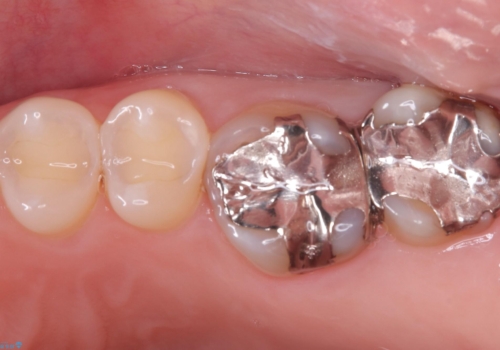

- 主訴:右下のセラミックのブリッジが何度も同じところで折れて壊れてしまう。

対合歯との咬合関係において、右下7番目と6番目の被せものの連結部がたわみやすい環境にあったため、ブリッジの新製ではなくインプラント治療を行いすべての歯を単冠仕上げとすることにしました。

何度も右下6、7間でブリッジが折れてしまうとのことでした。対合歯とブリッジの連結部が強く当たりたわみやすい状態でした。破折しずらい金属を使用したブリッジの選択もありましたが、支台歯(右下7)が失活歯場合、破折リスクが高く、破折してしまった場合にまたブリッジを外しての再治療になってしまう可能性を説明したところ、全て単冠仕上げとできるインプラント治療を希望されました。

右下5番のクラウンは、ブリッジを切断しそのまま使用していただいています。